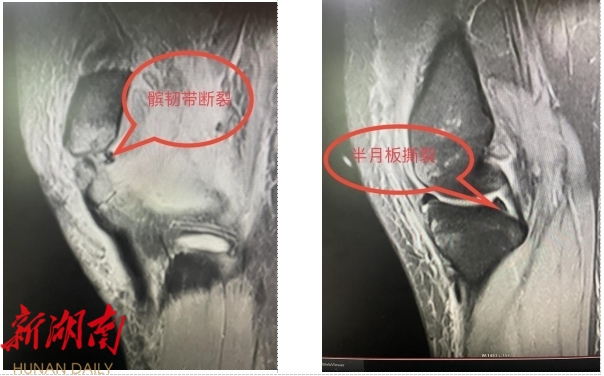

据悉,该患者因车祸导致膝关节严重损伤,半月板和髌韧带均受到不同程度的撕裂,髌骨更是发生了粉碎性骨折。患者在外院咨询医生后,均被告知需要进行多次手术才能解决下肢不同部位的损伤。而南华医院运动医学科团队在贺洪辉主任的带领下,迅速组织全科医师进行术前讨论,与患者及家属充分沟通,制定了详细的手术方案,为该患者实行一次手术,以解决左下肢多处损伤。

△术前影像